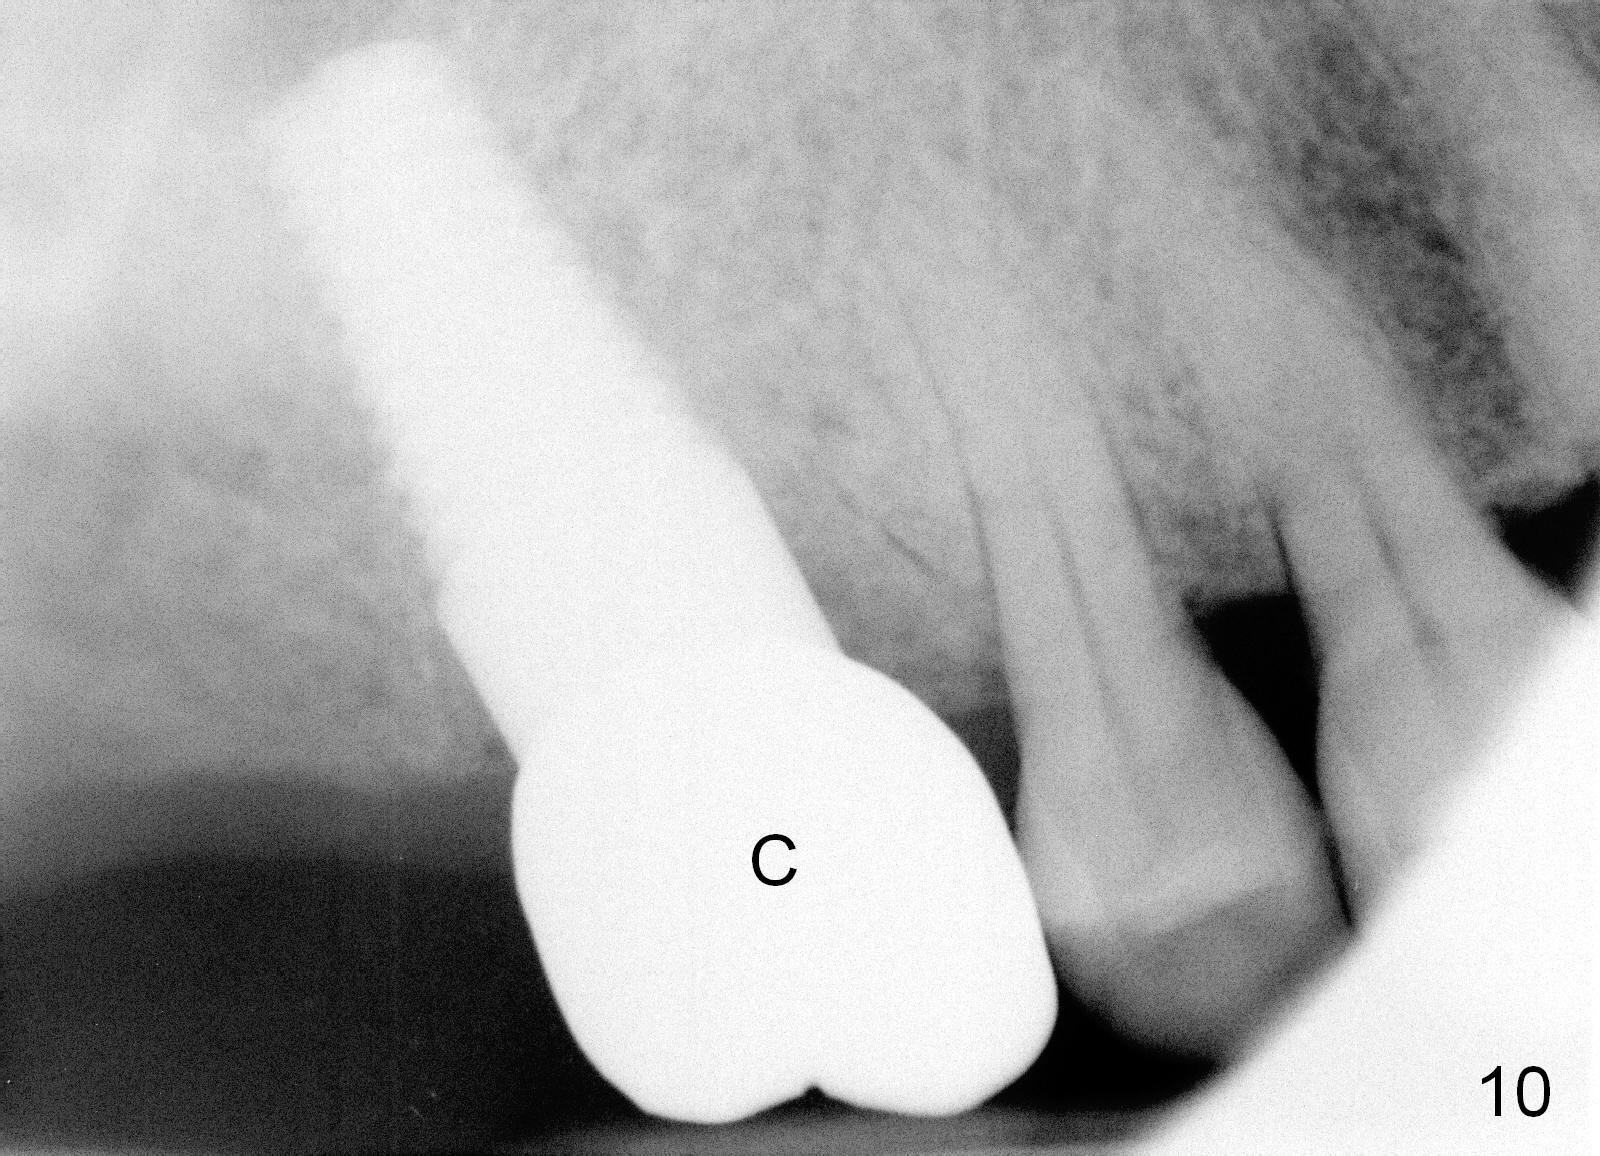

The upper right 1st molar fractures, the lingual portion mobile (Fig.1). There are deep pockets mesiolingually and distolingually. Fig.2 is preop PA, showing mesial bone resorption (*). The 84-year-old lady agrees extraction and immediate implant. Extraction is difficult due to not only root fracture but also hemorrhage. Following debridement of granulation tissue, the 3 sockets are packed with gauze for hemostasis. Even so, there is oozing from the bone. The septum can not be seen clearly. Its position is determined by an explorer. Osteotomes have to be used for osteotomy in the septum, followed by taps. The first intraop PA shows that 5x20 mm tap penetrates the sinus floor (Fig.3 ^). The osteotomy is further enlarged until 7x17 mm tap with stability (Fig.4). So far there has been no sign of sinus membrane perforation. Mixture of freeze dry mineralized bone and Osteogen is placed in the socket and pushed to the buccal and lingual walls as well as into sinus using a 4 mm flat end osteotome. A 7x17 mm implant is initially difficult to be inserted possibly due to blockage by bone graft. The osteotomy have to be recreated by a series of osteotomes and taps before placement of the 7x17 mm implant. It appears that the apical threads have been engaged into the sinus floor for primary stability (Fig.5). The insertion torque is 40 Ncm. According to our experience (1,2), this is not enough; finally the torque is increased to 60 Ncm by turning the implant more apically. The large implant obliterates the socket mesiodistally; the buccal and lingual gaps are filled with bone graft, followed by a collagen membrane (Fig.6 *) and suture. In order to protect the membrane, a short abutment is placed (A) and perio dressing (Fig.7*) is placed without occlusal interference. The abutment is removed 1 month postop, as the perio dressing has been dislodged. The patient returns for restoration 8 month postop. Bone regeneration occurs apparently in the coronal aspect of the implant (Fig.8), especially mesially (*, as compared to Fig.5). The gingiva-level implant is slightly subgingival mesially (Fig.9 M), probably due to high placement (compare to Fig.6). There is no bone resorption 6 months post crown (Fig.10 C) cementation.